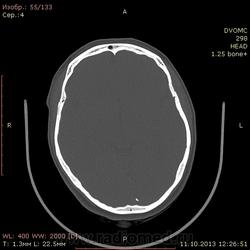

42 года. Слева в лобной доле кровоизлияние в 2011 году. Это понятно.

Есть другой вопрос нормальное ли обызвествление в затылочной доле?

Стоит ли судить о какой-то динамике имея только предыдущие КТ-снимки?

Ну, если предыдущие снимки есть, можно попытаться.